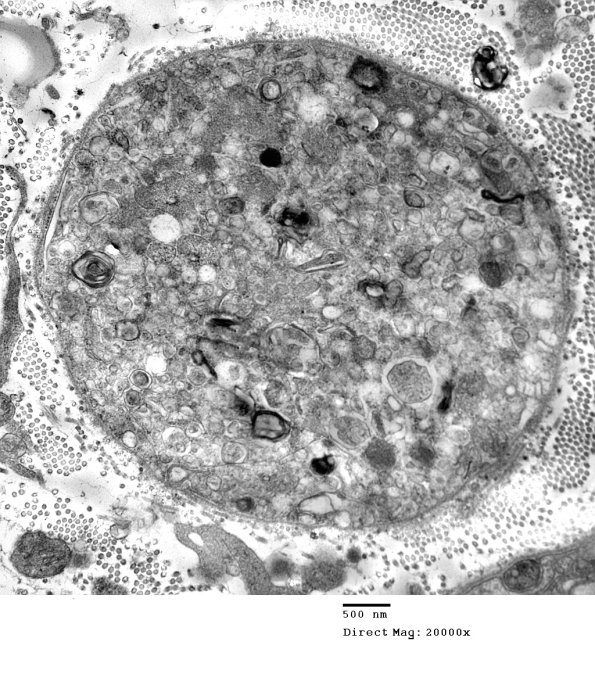

Established degeneration in this axon results in a Schwann cell containing myelin, axonal and Schwannian cytoplasm enclosed within the original Schwann cell basement membrane.